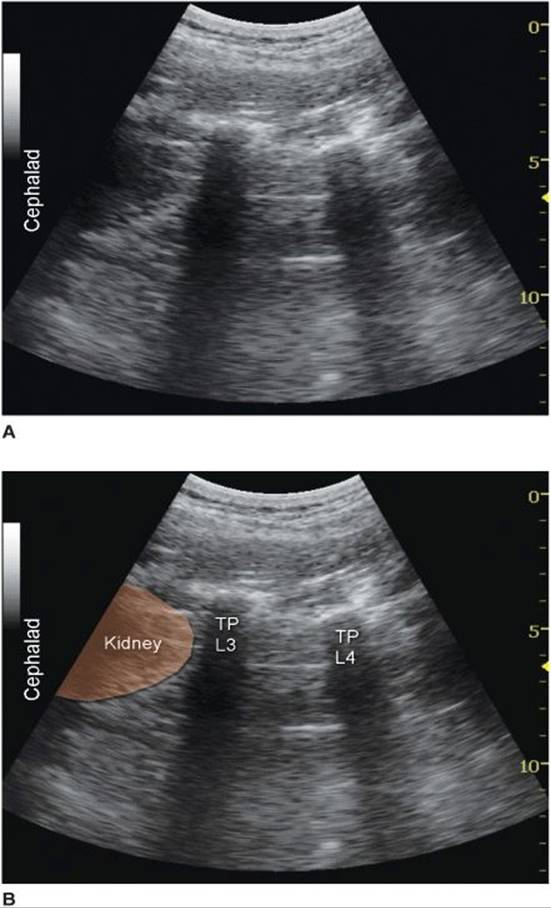

Regardless of the technique, the operator first should identify the transverse processes on a longitudinal sonogram (Figure 46-1). One technique is to first identify the flat surface of the sacrum and then scan proximally until the intervertebral space between L5 and S1 is recognized as an interruption of the sacral line continuity. Once the operator identifies the transverse process of L5, the transverse process of the other lumbar vertebrae are easily identified by a dynamic cephalad scan in ascending order. The acoustic shadow of the transverse process has a characteristic appearance, often referred to as a “trident sign” (Figure 46-2A). Once the transverse processes are recognized, the psoas muscle is imaged through the acoustic window of the transverse processes. The psoas muscle appears as a combination of longitudinal hyperechoic striations within a typical hypoechoic muscle appearance just deep to the transverse processes (Figure 46-2B). Although some of the hyperechoic striations may appear particularly intense and mislead the operator to interpret them as roots of lumbar plexus, the identification of the roots in a longitudinal scan is not reliable without nerve stimulation. This unreliability is partly due to the fact that intramuscular connective tissue (e.g., septa, tendons) within the psoas muscle are thick and may be indistinguishable from the nerve roots at such a deep location. As the transducer is moved progressively cephalad, the lower pole of the kidney often comes into view as low as L2-L4 in some patients (Figure 46-3A and B).

FIGURE 46-3. (A) Ultrasound image of the lumbar paravertebral space at the L2-L3 level demonstrating the lower pole of the kidney on the left-hand side of the image at approximately 5 cm depth. (B) Labeled ultrasound image of the lumbar paravertebral space at L2-L3 level demonstrating the lower pole of the kidney on the left-hand side of the image at approximately 5 cm depth. TP, transverse process.